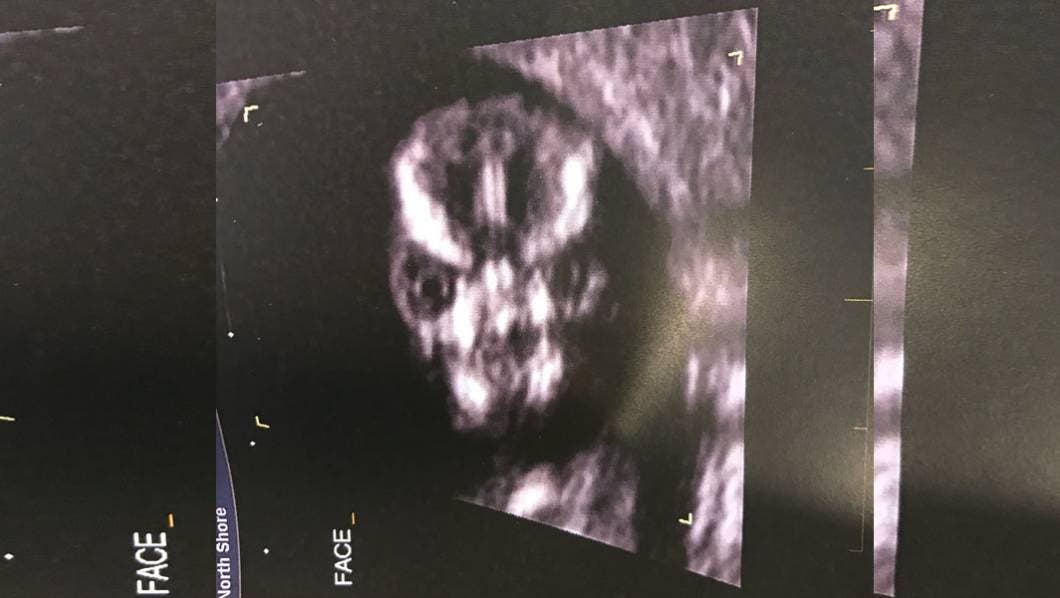

Pero para finalizar con las burlas, decidió subir otra imagen del ultrasonido, en la que se ve mucho mejor.